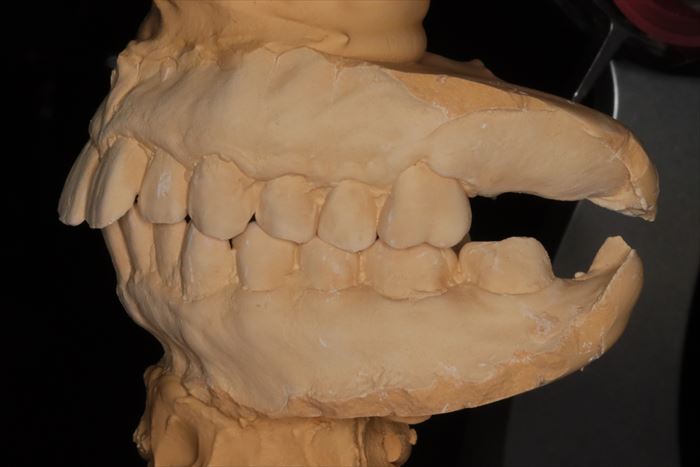

いつものように上下歯列の型取り(印象採得)とフェイスボウトランスファー(顔弓計測)を行います。

フェイスボウトランスファーの記録を利用してKaVo プロター evo7 咬合器に上下歯列石膏模型をマウントしました。

インプラントを埋入する部位を石膏模型上で確認します。